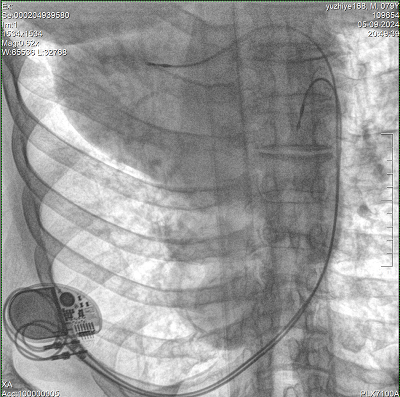

具備血管造影及數(shù)字減影(DSA)、路徑圖(Road-map)、透視、攝影等功能。 廣泛適用于介入科、血管外科、腫瘤科、消化內(nèi)科及骨科等多個臨床科室,典型應(yīng)用包括:TACE(肝腫瘤栓塞與化療灌注術(shù))、心臟起搏器置入術(shù)、四肢動脈造影術(shù)、下肢靜脈濾器置入術(shù)、ERCP(經(jīng)內(nèi)鏡逆行胰膽管造影術(shù))等。

Clinical picture

臨床圖片